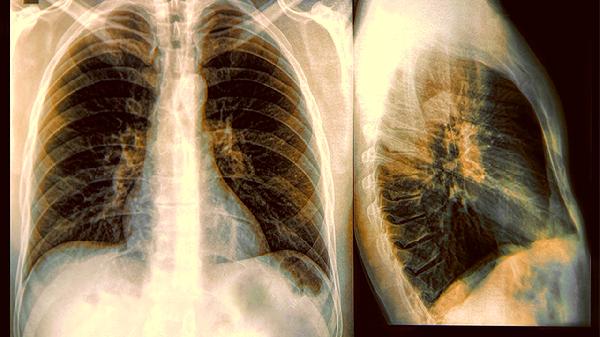

改變生活習慣比吃藥手術更重要。每週給家裏做次大掃除時,記得重點關照這些高危物品。空氣淨化器不能完全解決問題,定期開窗通風才是王道。當出現持續兩周以上的刺激性乾咳、痰中帶血絲時,別猶豫,儘快去拍個低劑量CT。